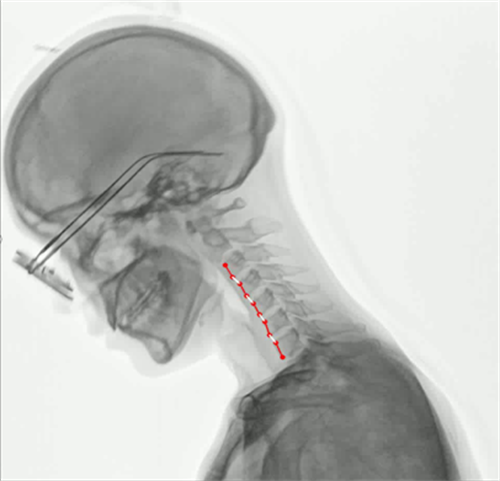

③功能化。当然随着未来对疾病的诊断以及预后评估,功能化发展必然是DR的发展趋势。在肺功能上的应用,可以通过测量呼吸流速、流量分析、肺部通气功能分析等,直观的展现出患者呼吸过程中的通气异常区域,对通气异常及COPD患者提供影像学诊断全新的技术手段。对肺部进行血流灌注分析,来实现在无造影剂条件下对肺栓塞进行评估。还可以应用于骨骼运动方向研究,例如颈椎运动功能成像,骨折修复后愈合状态的评估等。(左边第一张图为肺部血流灌注成像,右边两张图为颈椎运动功能成像)